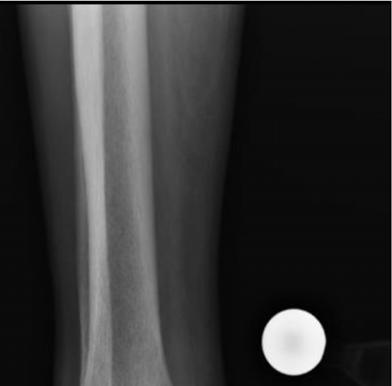

921 Charcot Neuroarthropathy of the Foot and Ankle in the Acute Setting: An Illustrative Case Report and Targeted Review

Duringthestudyperiodatotalof21participants comprising19residents(sixpostgraduateyear[PGY]1,